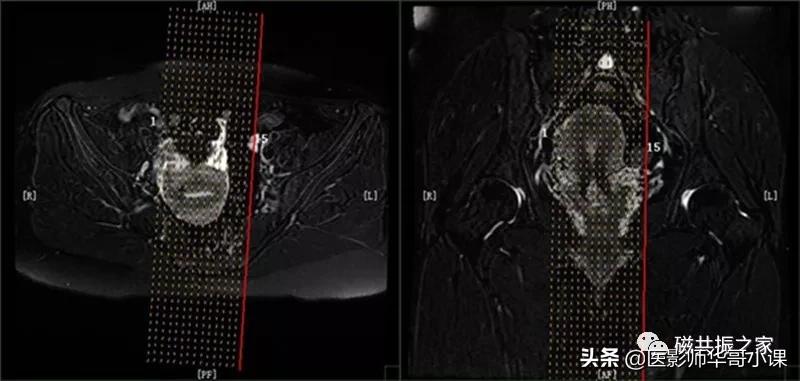

冠状位: COR T2 FS FSE 冠状面T2脂肪抑制序列

在横轴位和矢状位上定位,在矢状位上找到显示子宫全长最好的层面,如需了解宫颈病变,使定位线平行于宫颈管长轴(图A),如需了解子宫内膜病变,使定位线平行于子宫内膜长轴。在横轴位上找到显示子宫最大的层面,使定位线平行于当前子宫内膜长轴,扫描范围包括整个子宫及两侧附件,需包括整个病变范围。

冠状位是显示卵巢及子宫附件较为理想的方位。